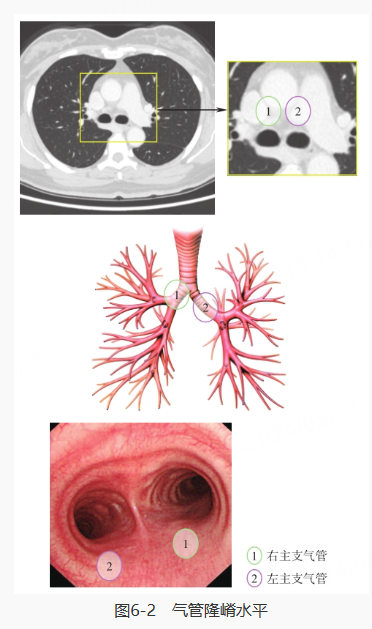

镜头探入,到达气管隆嵴水平: